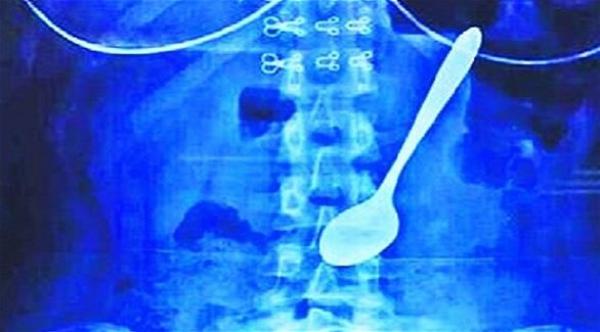

ونقلت يوي الى المستشفى حيث أظهرت أشعة X ملعقة معدنية استقرت في بطنها، بحسب ما ذكرت صحيفة "بيبلز دايلي اونلاين" الصينية. واستخدم الأطباء الأسلاك لإخراج الملعقة التي استقرت في منطقة ضيقة عبر إدخالها إلى المريء والمعدة.